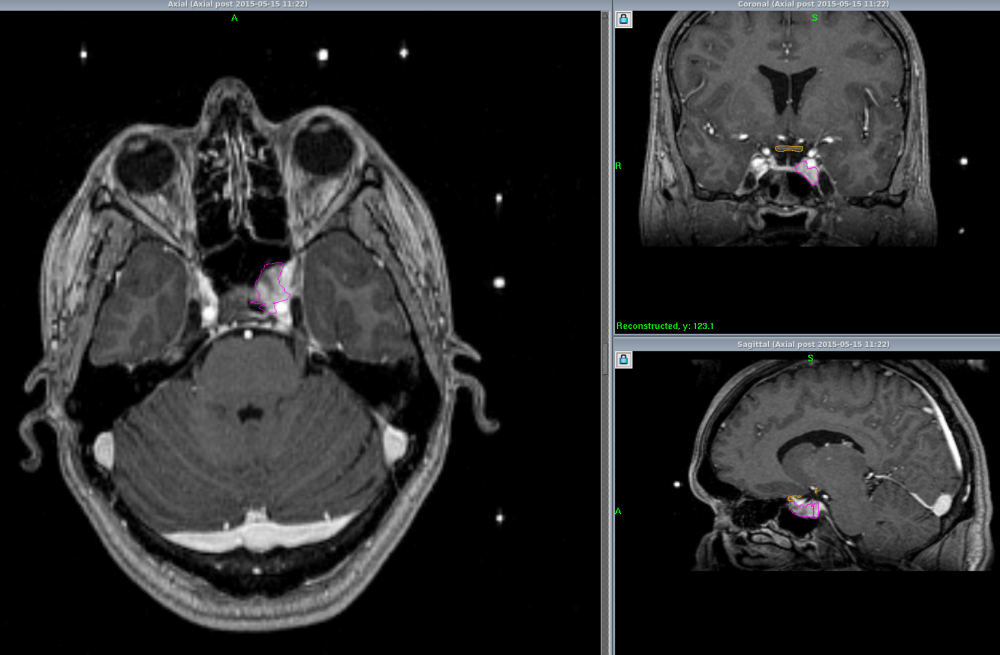

Pituitary Adenoma

The pituitary gland lies in the sella turcica (a saddle shaped cavity at the base of the skull) and is attached to the brain by the pituitary stalk. Tumours may produce hormones in excessive amount or cause damage by pressing on the nerves on their way to the eye.

Gamma Knife Radiosurgery is effective in halting the growth of the tumour and if the optic nerve/chiasm is not too close, then sufficient dose can be given to stop the abnormal hormone production. Large tumours have to be reduced by operation or medication first.